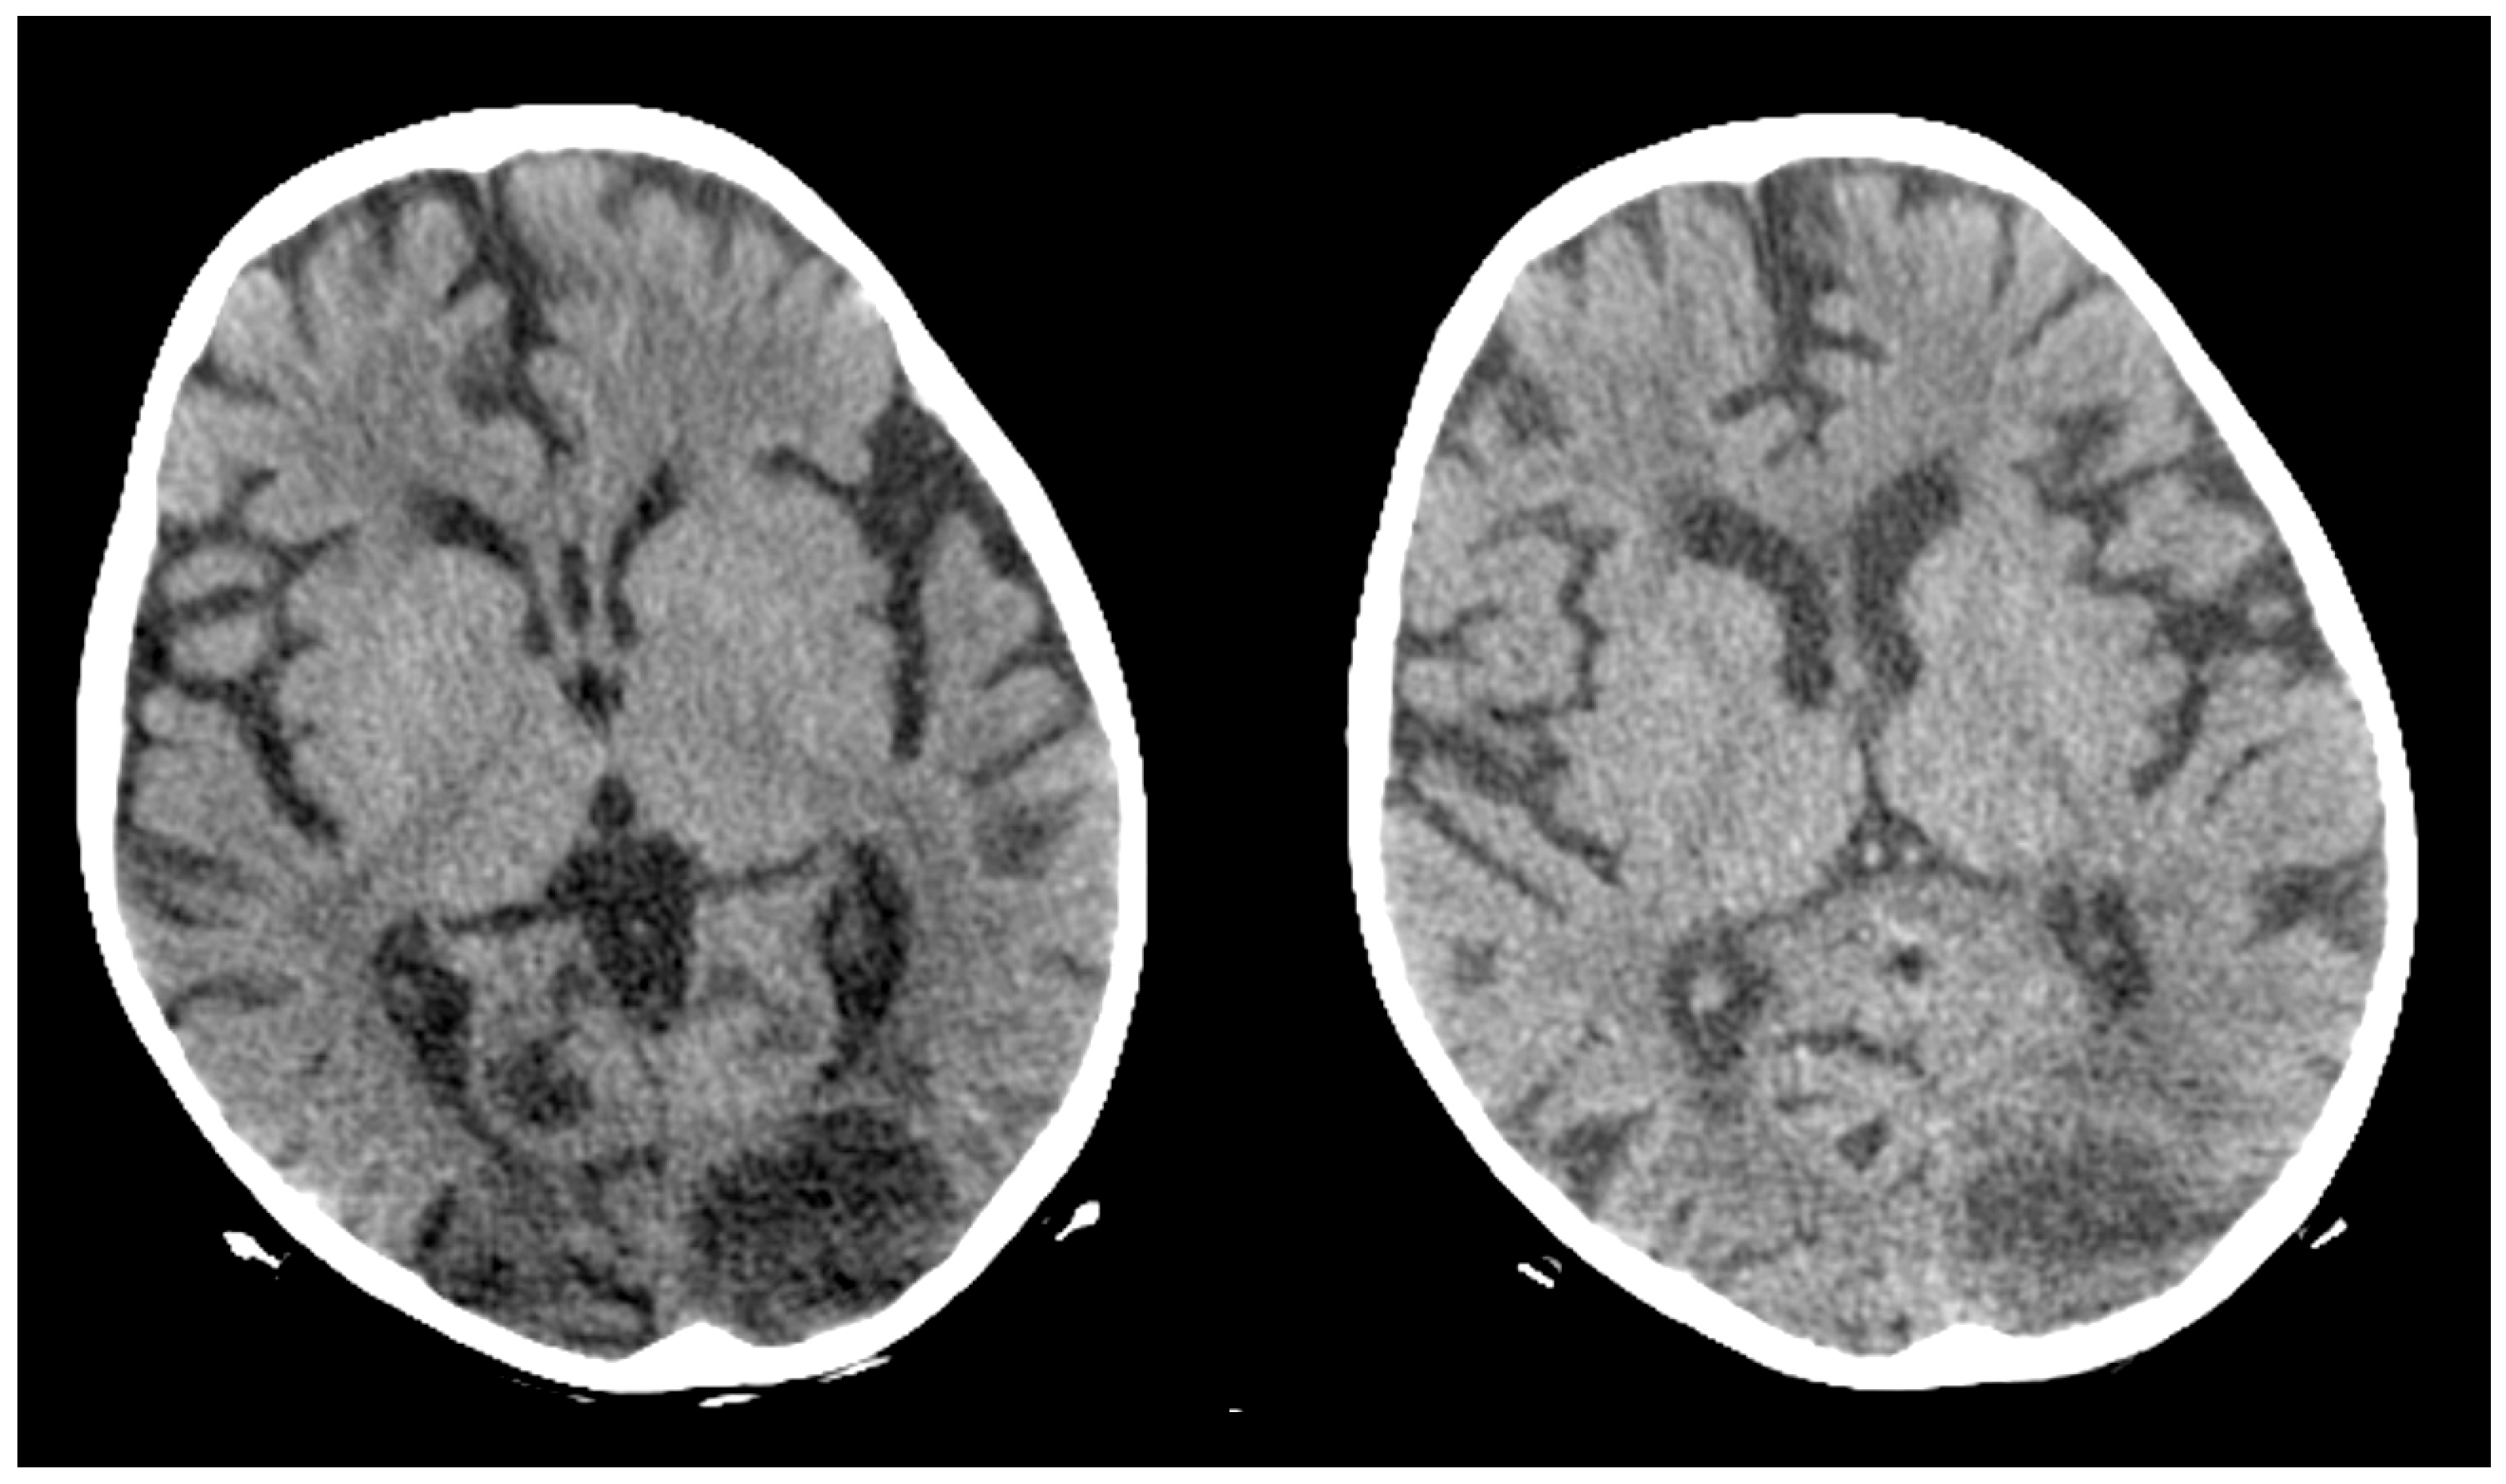

A Rare Case of Rhizomucor pusillus Infection in a 3-Year-Old Child with Acute Lymphoblastic Leukemia, Presenting with Lung and Brain Abscesses—Case Report

2. Case Report

Pahnev, Y.; Avramova, B.; Gabrovska, N.; Dontcheva, Y.; Tacheva, G.; Minkin, K.; Kreipe, H.; Yurukova, N.; Penkov, M.; Kartulev, N.; et al. A Rare Case of Rhizomucor pusillus Infection in a 3-Year-Old Child with Acute Lymphoblastic Leukemia, Presenting with Lung and Brain Abscesses—Case Report. Infect. Dis. Rep. 2026, 18, 2. https://doi.org/10.3390/idr18010002